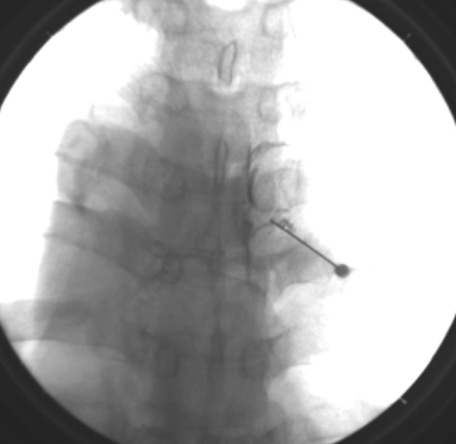

骨の後ろは超音波のビームが届かないので脊髄の近くや骨で隠れたりするところははなかなか行うことができないのです。狙った場所へ安全に針を持っていき造影剤を注入することで的確に処置ができるということです。

こちらは胸部の神経根ブロックですが、椎弓に当ててから滑らせて潜らせるなどいろいろ工夫して行うのです。

透視画像